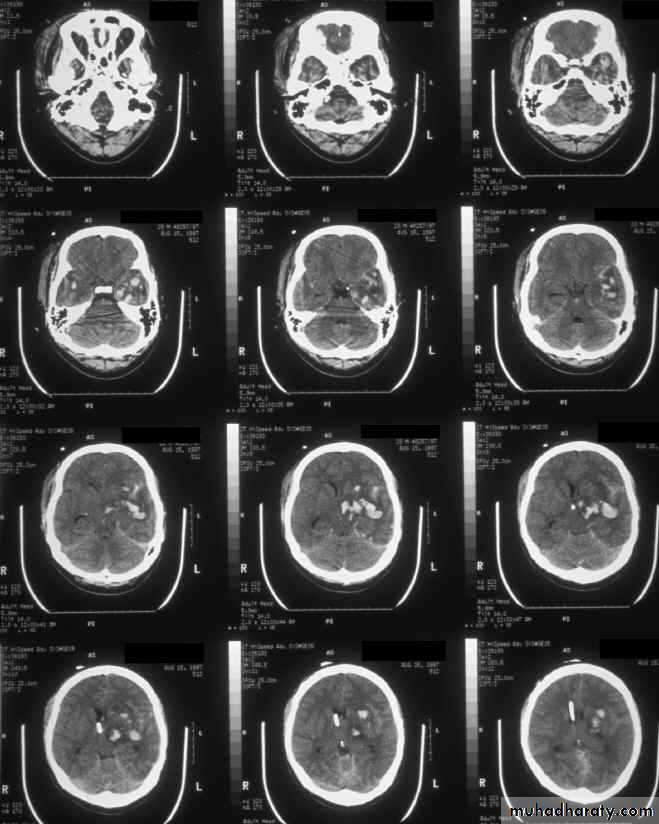

c. Intracerebral Haematoma

This is the least common of traumatic haematoma.They are due to areas of traumatic contusion coalescing into a contusional haematoma.

Disrupted cerebral tissue release thromboplastins that potentiate haemorrhage.

CT scan: appear as hyperdence lesions with associated mass effect and midline shift.Large intracerebral haematomas should be evacuated unless the patient’s neurological state is improving.

Small inracerebral haematomas may not require removal, but be aware that they can expand.